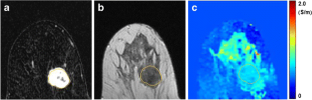

Fig. 2